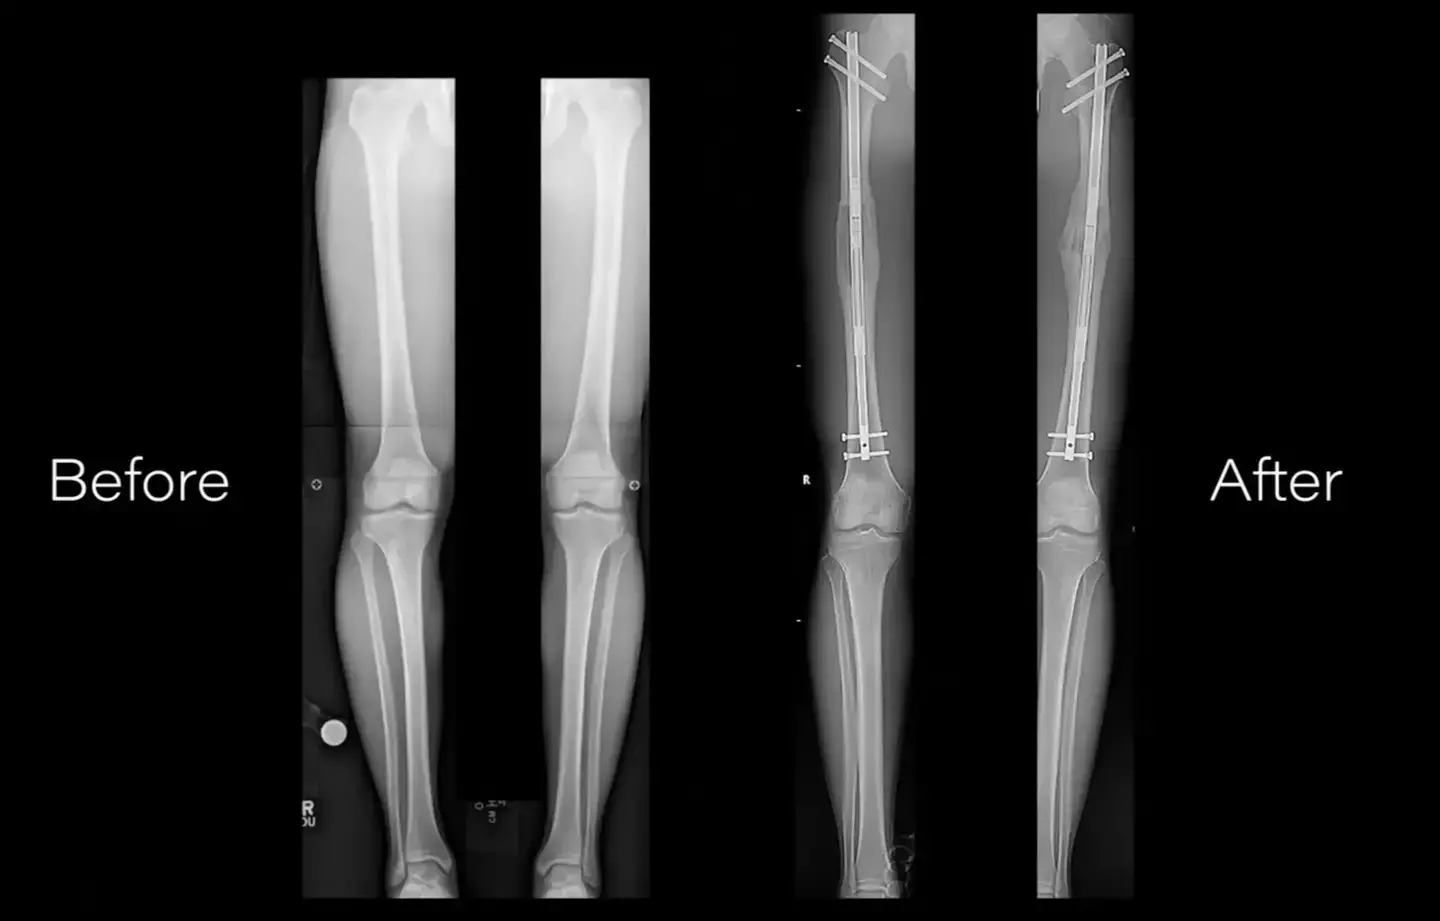

In a video uploaded to YouTube by NuVasiveInc, we quickly learn surgeons perform an osteotomy by cutting the affected bone into two segments.

A series of metal pins and braces are then implanted to the area around a break with a little screw sticking out.

The first involves an external fixator, which sees a metal frame usually sticking out several inches from the body.

Another option is to place an internal rod inside of the bone, and it's more aesthetically pleasing (I guess), as it's not seen outside of the body.

This gradually stretches out the leg as the bone is healing, until the point of desired length is reached for the patient.